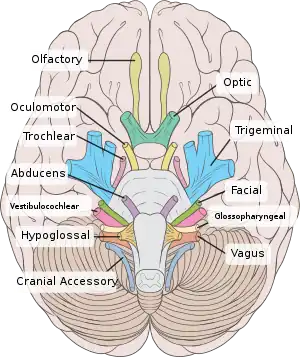

Inferior view of the human brain, with the cranial nerves labelled.

Inferior view of the human brain, with the cranial nerves labelled. Mandibular division of the trifacial nerve.